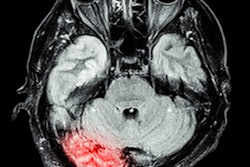

Four separate patients with large-vessel occlusions correctly predicted by the algorithm. The top row shows a representative CT slice from the delayed venous-phase CT angiography scans. The middle row shows the preprocessed maximum intensity projection images that function as the input to the model. The bottom row are overlaid heat maps, with areas in red showing the most discriminative regions. These so-called hot regions correlate with the occlusion location (respectively: left [L] M2, L M1, right [R] M2, basilar) in each patient. Images and caption courtesy of the RSNA.The researchers found that using combinations of phases -- and especially all of the phases -- led to a higher AUC for detecting LVO stroke than single-phase CTA. The additive effect from combining additional delayed phases with phase 1 indicated that findings of both initial absence of opacification and delayed enhancement were important factors in producing better algorithm performance, according to the researchers.